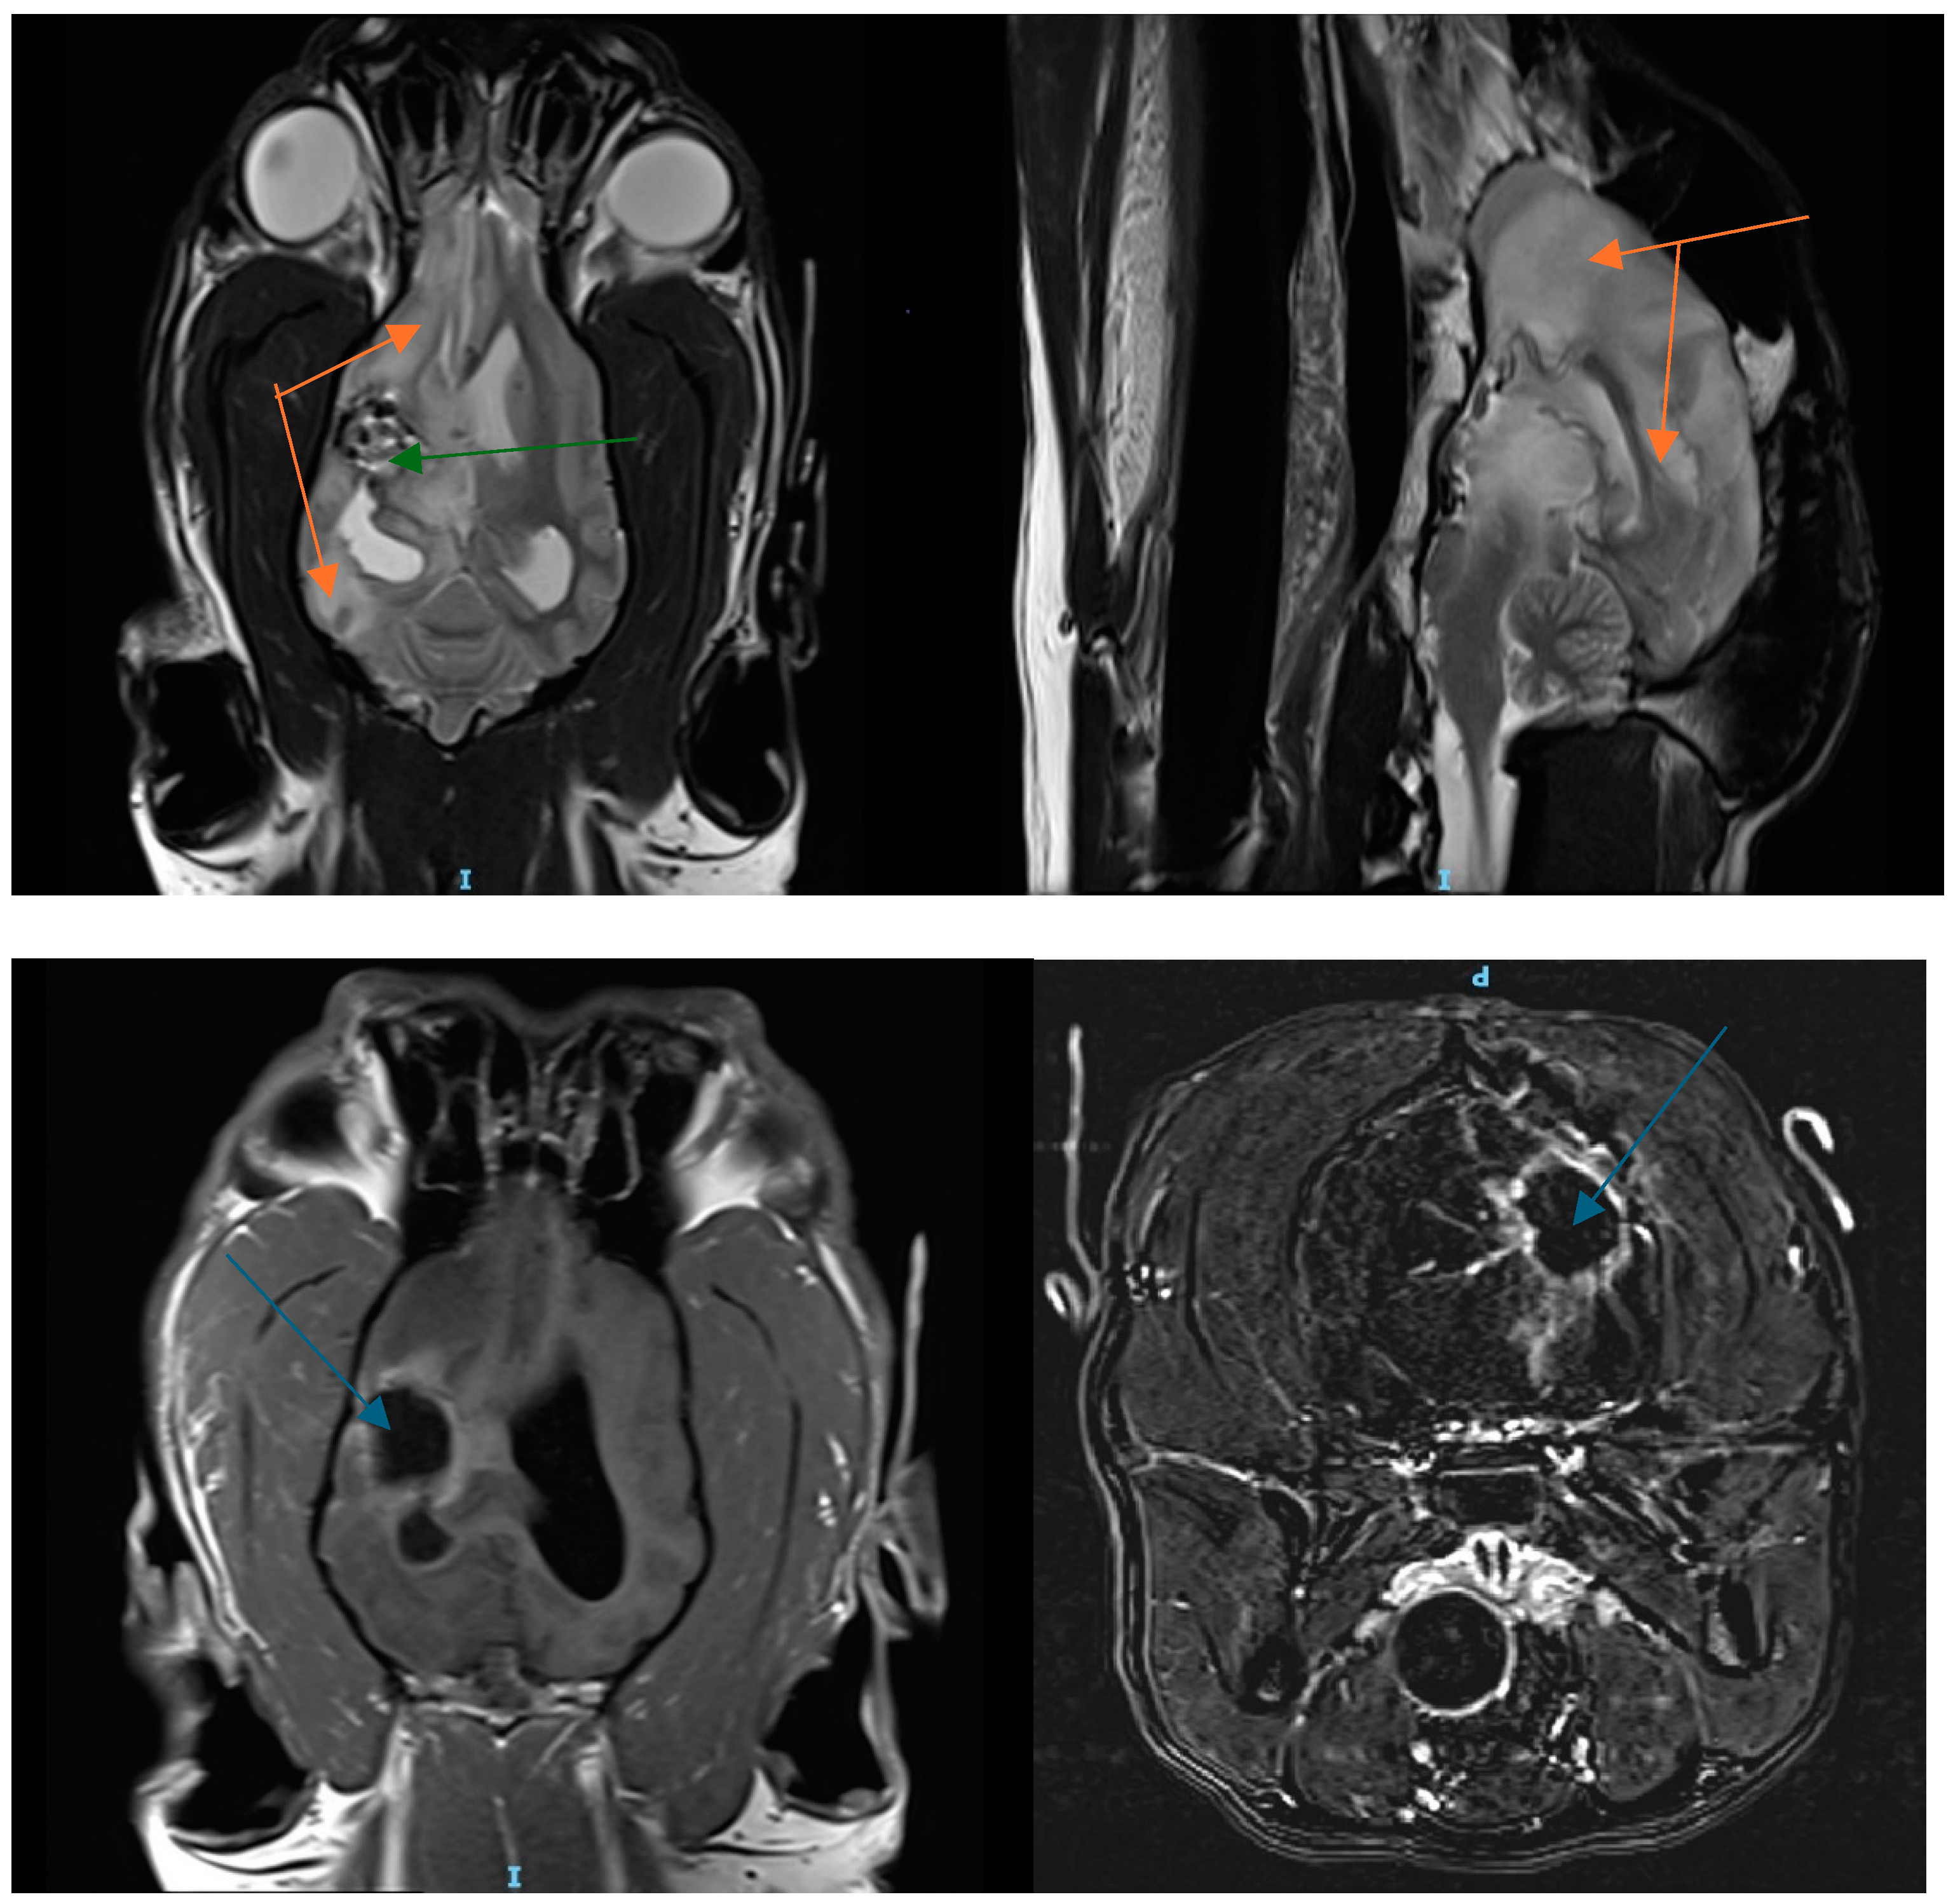

3.1. Patient History